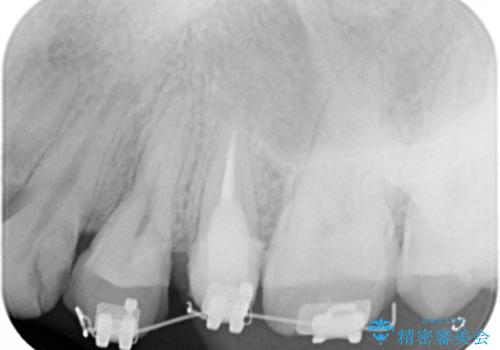

虫歯が大きかったことから、神経の温存はできたものの歯ぐきよりも深い虫歯の問題を解決するため、部分矯正治療を併用したセラミック治療を行うこととしました。

当初、歯ぐきよりも深い虫歯の存在や、歯のポジションに問題がありましたがマルチブラケットを用いた部分矯正で行うことで歯の挺出同時に適切な位置へと歯を移動させ、歯周環境を整えたセラミック治療を行うことができました。